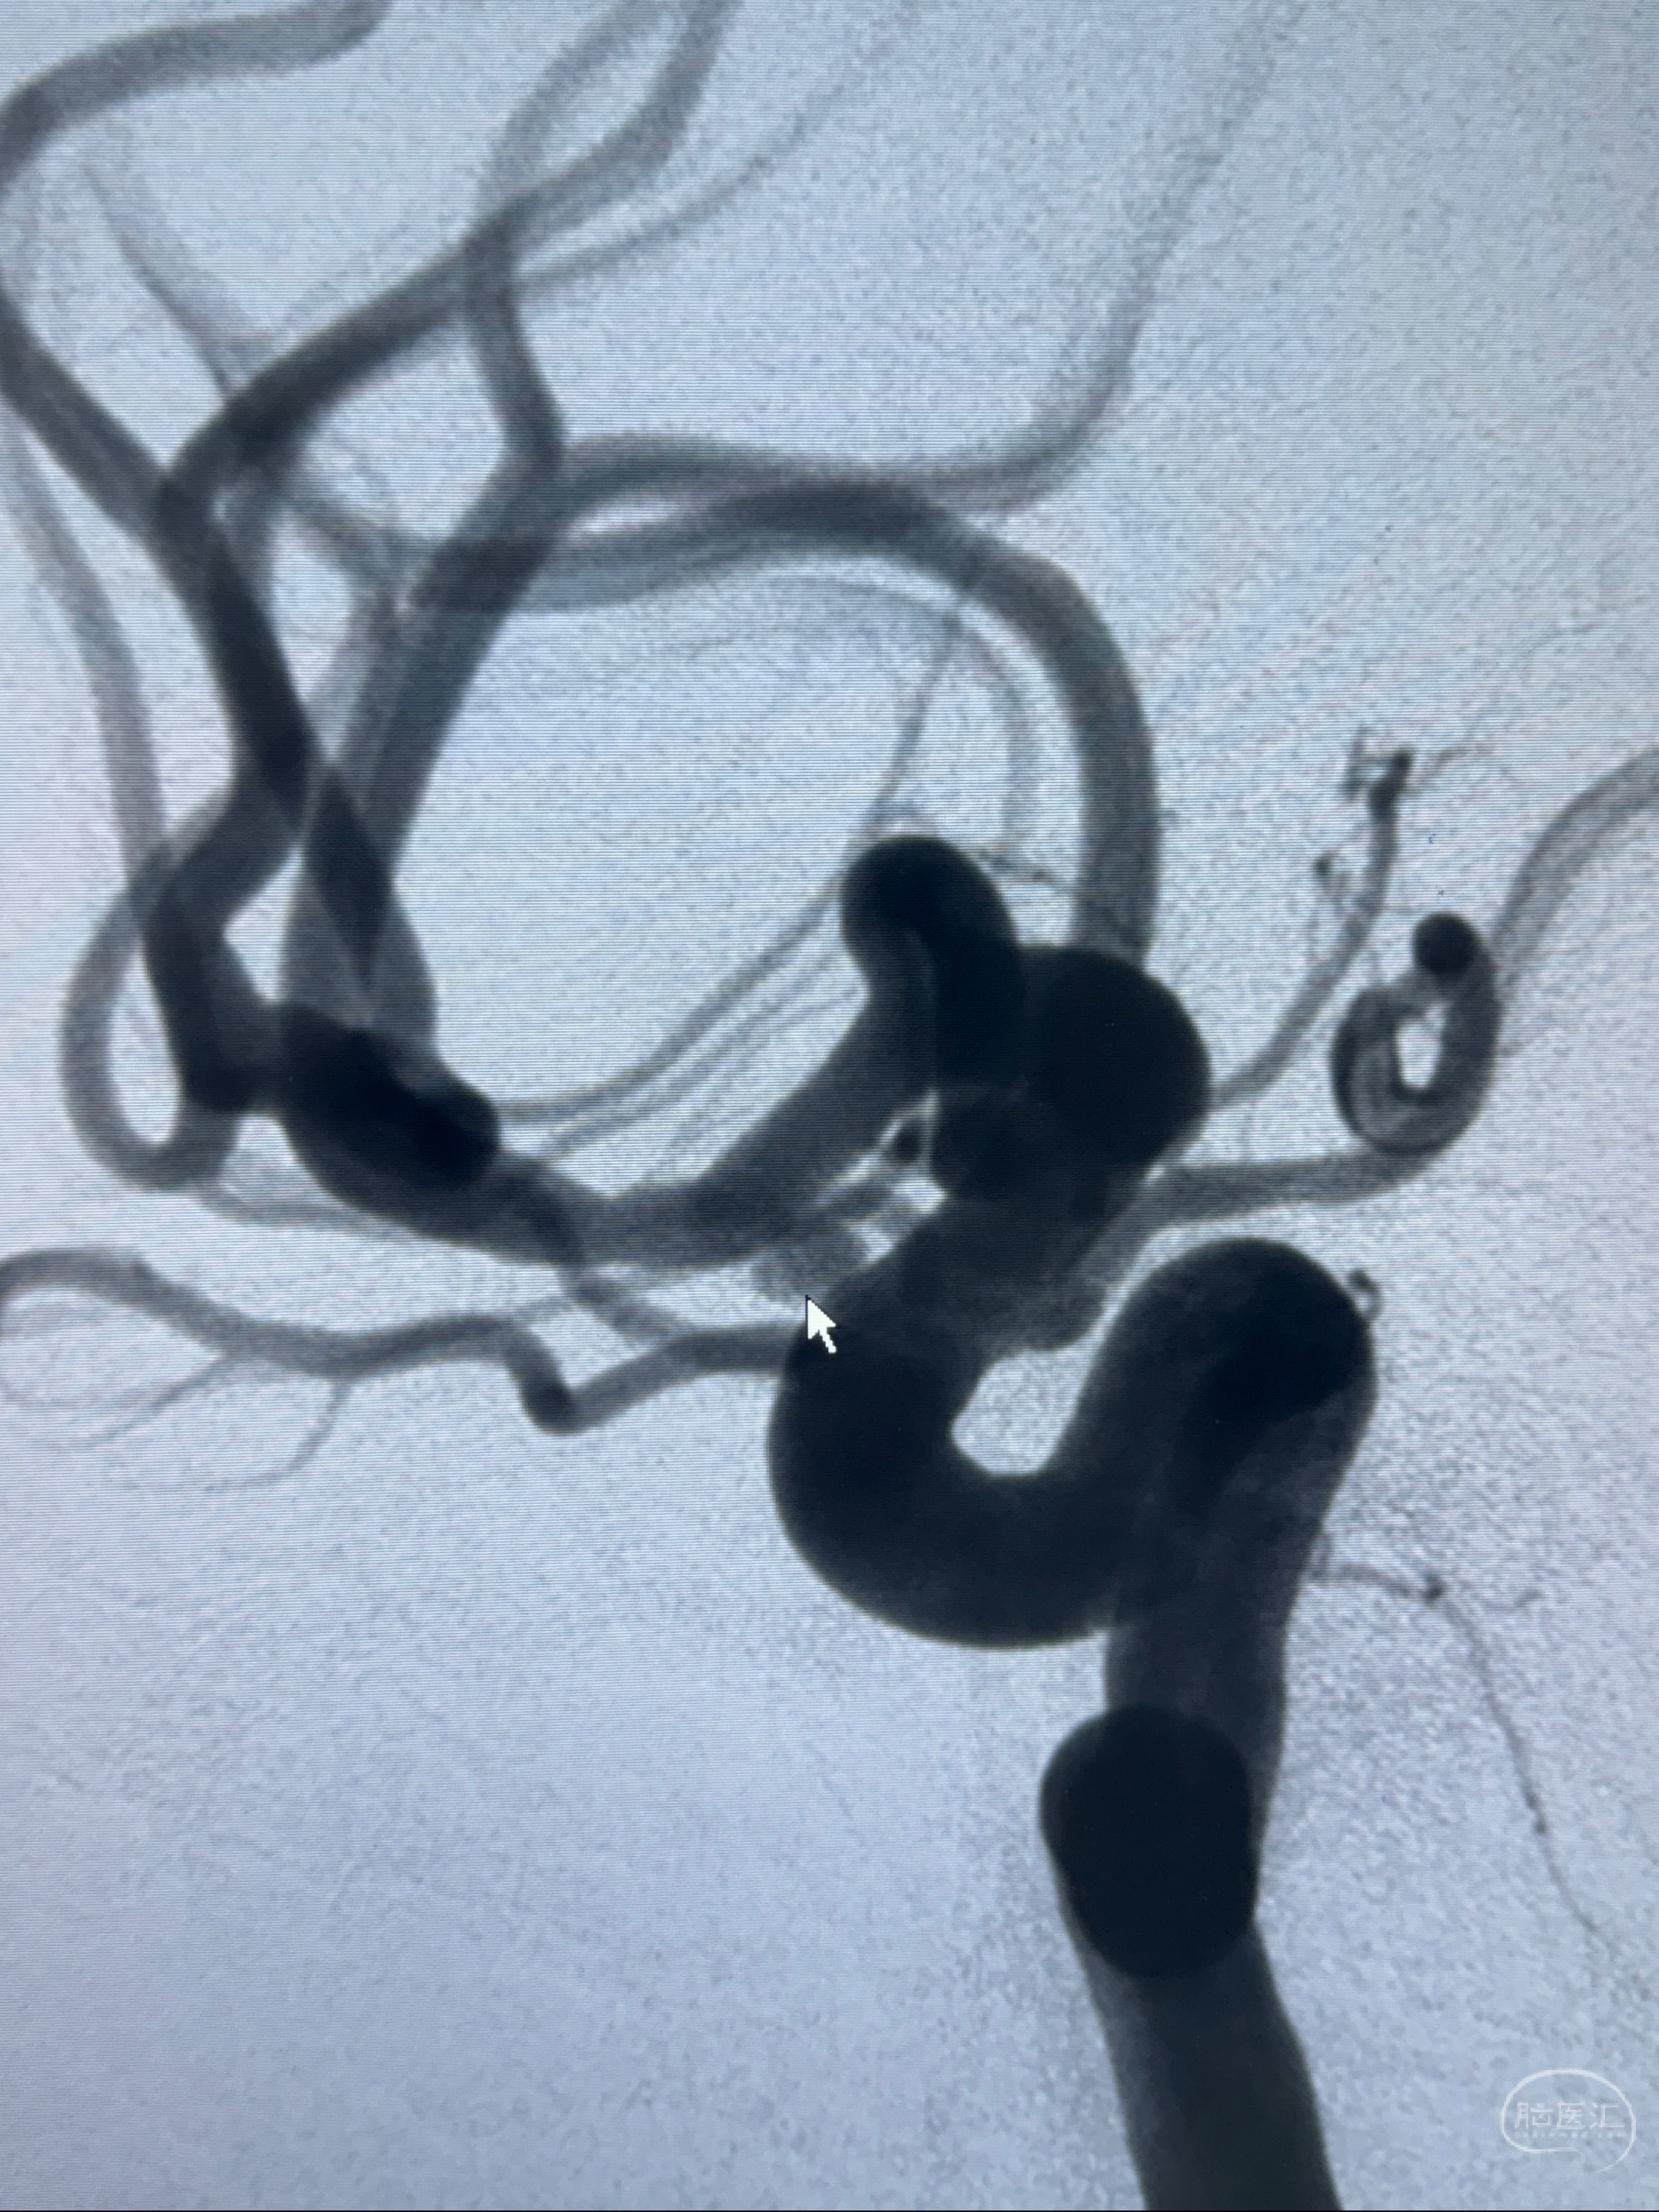

2023-11-24DSA:右侧大脑中动脉下干起始部动脉瘤,约2.3*2.5mm,形态规则

治疗策略:

- 随访?

- 夹闭?

- 单弹簧圈填塞?

- 支架辅助治疗?

2023-12-04全麻下行支架辅助治疗

S-AB4-20mm